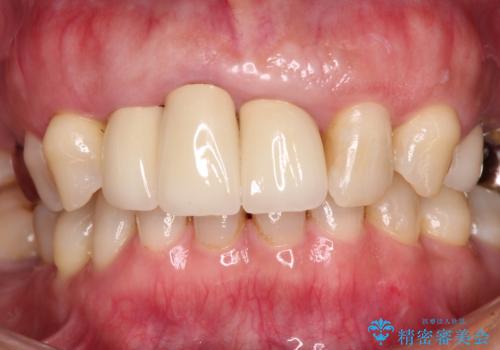

歯肉の位置は変更できないため、露出している歯根をクラウンで覆い隠すと歯が長く見えることを事前にお伝えしておりました。

真ん中2本は治療前よりも短めに仕上げることで、極端に長い印象を避けることができました。